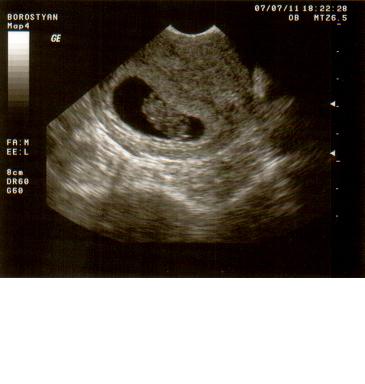

Négy órás kórház kálvária(kettőbe voltam-honvéd,szabolcs utcai)mert szervezetlenség van ézt a bőrömön tapasztaltam.Kihívta a férjem a mentőt,mert látszólag senkinek nem volt baja,leszámítva,hogy reszkettem mint a kocsonya,de aggódtunk a Bogyók miatt.Kemény volt a pocim,de szerintem a stressz miatt.Volt ctg,ultrahang,méhszájvizsg.ha valakit részletesebben érdekel,leírom.az elsőbe írtam,most nem akartam...